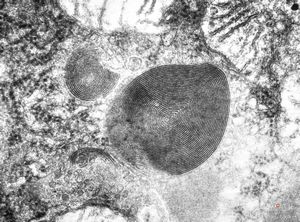

M,15y. | megamitochondria with lamellar inclusions in hepatocyte - Wilson disease